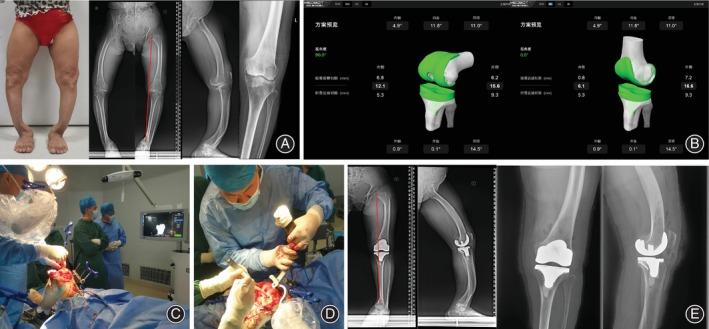

Total knee arthroplasty (TKA) is a well-established treatment for end-stage knee osteoarthritis. However, in patients with concomitant extra-articular deformities, conventional TKA techniques may lead to unsatisfactory outcomes and higher complication rates. This review summarizes the application of navigated TKA for treating knee osteoarthritis with extra-articular deformities. The principles and potential benefits of computer navigation systems, including improved component alignment, soft tissue balancing, and restoration of mechanical axis, are discussed. Research studies demonstrate that navigated TKA can effectively correct deformities, relieve pain, and improve postoperative joint function and quality of life compared with conventional methods. The advantages of navigated TKA in terms of surgical precision, lower complication rates, and superior functional recovery are highlighted. Despite challenges like the learning curve and costs, navigated TKA is an increasingly indispensable tool for achieving satisfactory outcomes in TKA for knee osteoarthritis patients with extra-articular deformities.

全膝关节置换术(TKA)是治疗膝关节晚期骨关节炎的成熟方法。然而,对于伴发的关节外畸形患者,传统的 TKA 技术可能导致不满意的结果和更高的并发症发生率。本综述总结了计算机导航 TKA 在治疗伴发关节外畸形的膝关节骨关节炎中的应用。讨论了计算机导航系统的原则和潜在益处,包括改善组件对线、软组织平衡和恢复机械轴。研究表明,与传统方法相比,导航 TKA 可有效矫正畸形、缓解疼痛,并改善术后关节功能和生活质量。导航 TKA 在手术精度、较低的并发症发生率和更好的功能恢复方面的优势得到了强调。尽管存在学习曲线和成本等挑战,但导航 TKA 是实现膝关节骨关节炎伴发关节外畸形患者 TKA 满意结果的不可或缺的工具。